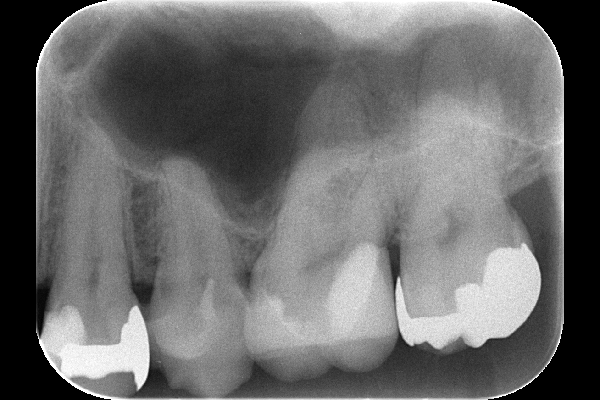

レントゲンでは手前の歯との間の面に深い虫歯があることが確認できました。術前の検査では神経に反応があり生きていることを確認し、神経を残す治療を行います。

2.術前のレントゲン写真

矢印の部分に深く進行した虫歯が確認できます。神経(歯髄)は検査で生きていることが確認できたため、残すための治療を行う方針となりました。